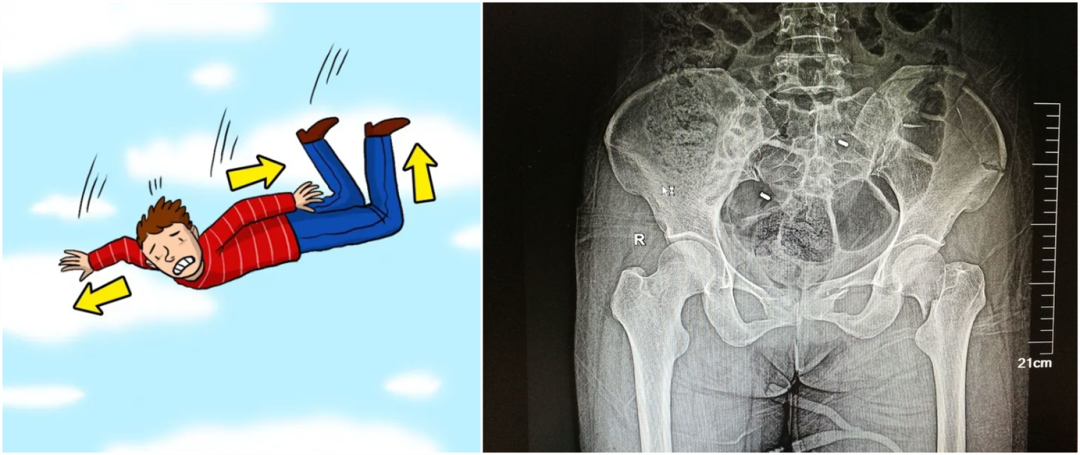

從暴力的大小來看,還可以細分為高能量的損傷和低能量的損傷。比如說,如果是車子撞的,從高處墜落,通常會造成高能量的損傷,而普通的跌倒造成的骨折,一般不太嚴重,可以說是低能量的損傷。

【醫療科普】:不穩定性骨折影像

不穩定性骨折